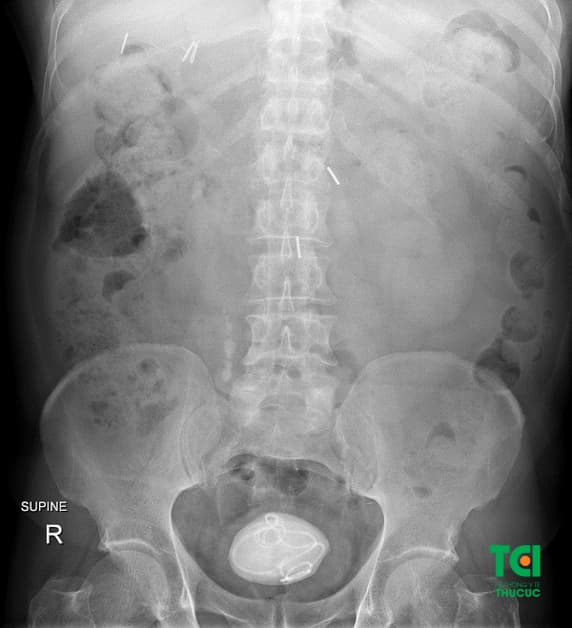

Để có chẩn đoán chính xác về sỏi bàng quang, người bệnh sẽ được chỉ định thực hiện một số các xét nghiệm, chẩn đoán hình ảnh hệ tiết niệu như: xét nghiệm máu, tổng phân tích nước tiểu, siêu âm ổ bụng – tiết niệu, chụp X – quang vùng tiết niệu, chụp CT – Scanner nếu cần thiết, có thể nội soi bàng quang để xác định sỏi.

Hình ảnh sỏi bàng quang hiển thị qua phương pháp chẩn đoán chụp X – quang